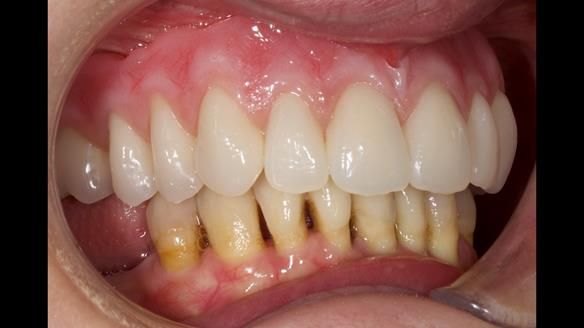

She had previously suffered from generalised periodontitis – stage IV, grade C, currently stable, with reduced attachment across the upper arch.

By the time she came to me, her periodontal condition was stable — but the aesthetics in the upper jaw were very poor.

We provided her with an immediate upper denture (Mk 1), followed by a definitive metal-based upper denture (Mk 2). A lower removable partial denture was discussed, to be made only if needed once the upper treatment was complete. However, at review, this wasn’t necessary — Adnana had excellent neuromuscular control and function, even with a shortened dental arch (SDA).

- Immediate denture (Mk 1) fitted the same day the teeth came out

- Definitive denture (Mk 2), metal-based and custom-designed for her face

- A restored smile, restored lip support, and a patient who owned the journey